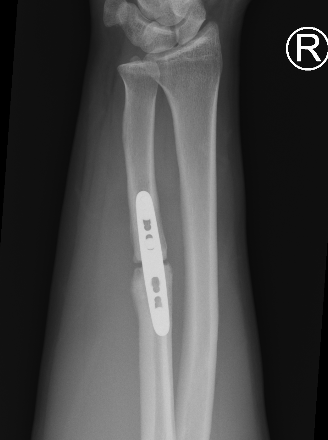

Nonunions

Ulna nonunion after plating